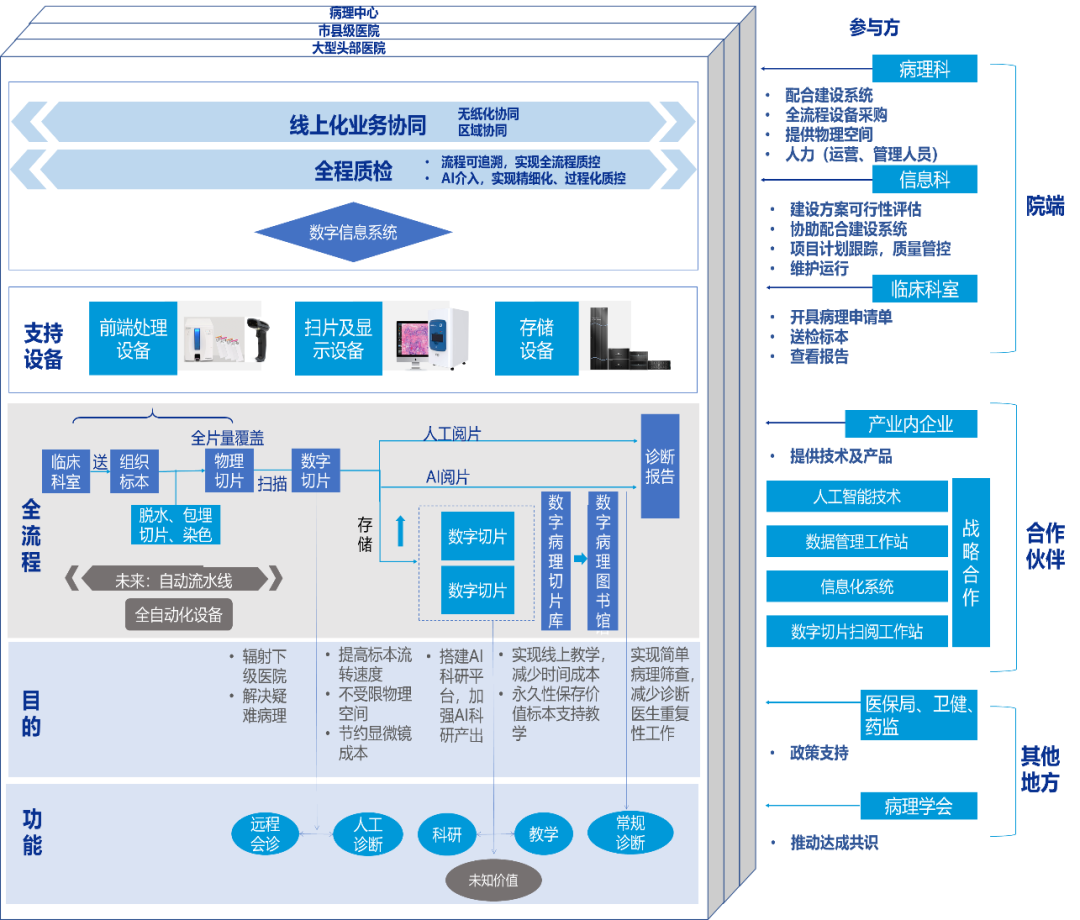

工作流程对比图

工作流程对比图

来源:商汤科技